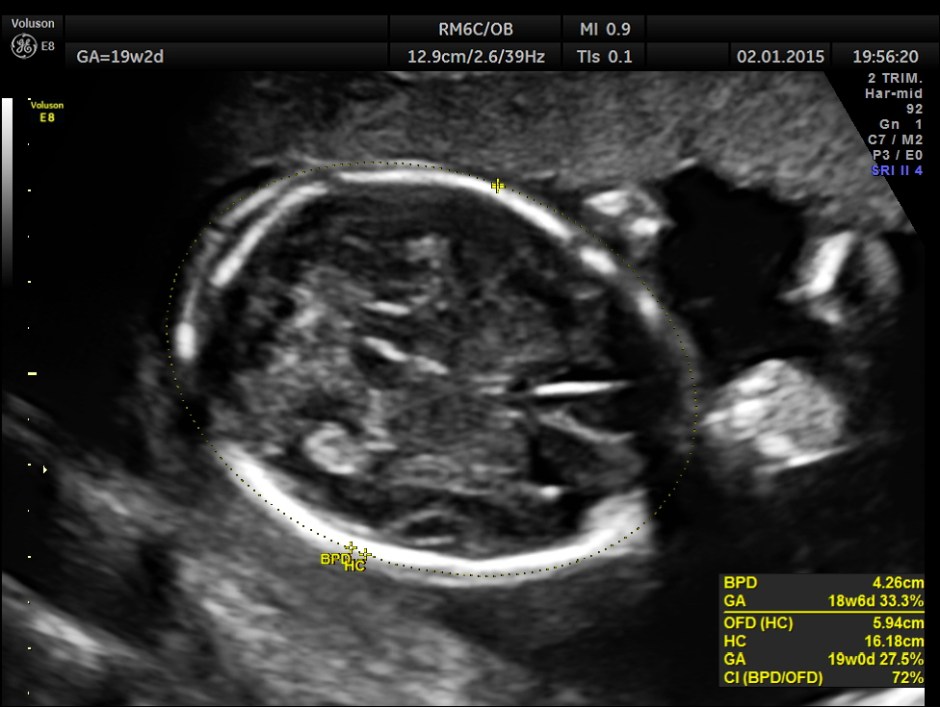

A 20 year old lady , 2nd gravida with one live normal child and history of consanguinity was referred for 2nd opinion for suspected cardiac anomaly.

The rest of the scan findings were normal.

This fetus had a large pericardial effusion with structural defect of the heart – VSD and disproportionately smaller left heart – possibly co-arctation of aorta . The patient was advised chromosomal studies and was lost for follow up.